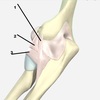

221

radial collateral ligament

2

223

lateral ulnar collateral ligament - holds the ulna in place

225

annular ligament

230